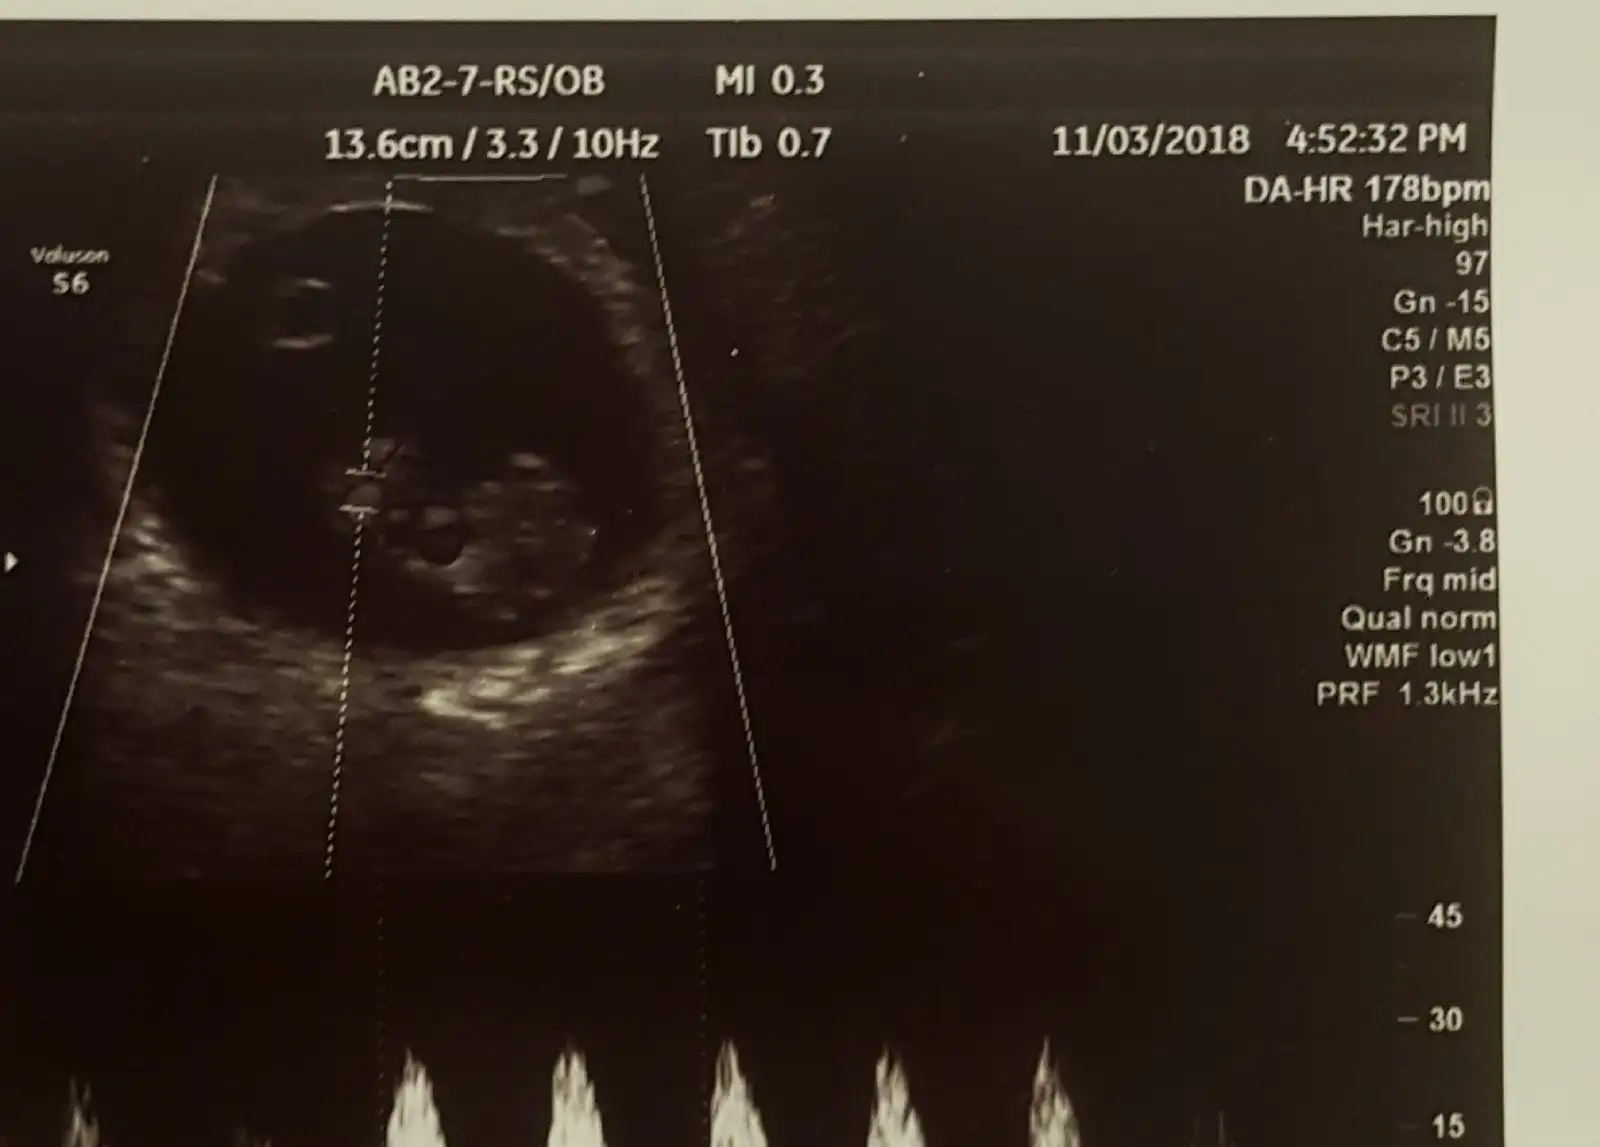

Sagda ustte da hr 178 bpm yaziyor 20181116_211351.webp

Yalniz bu hep degisiyor ki ben bi gittigimde 141 di sonra 160 oldu en son bu oldu .bu tahminde hafta olayida var mi ki acaba